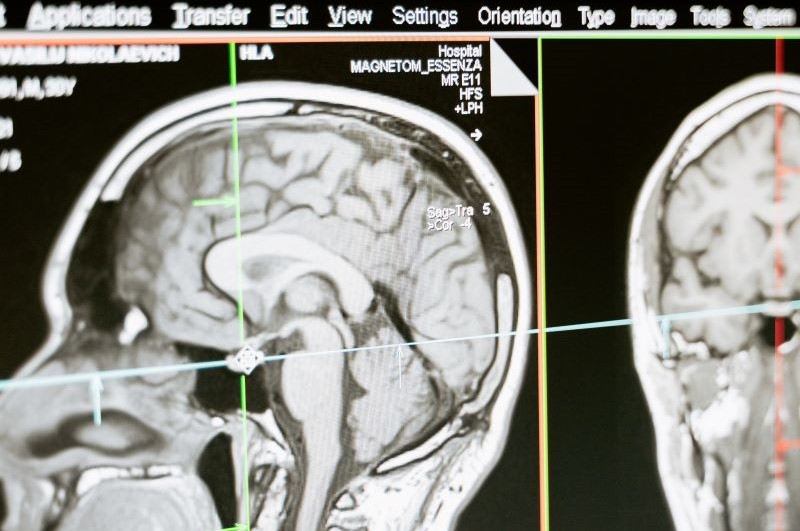

-Durchführung von Untersuchungen mithilfe von Bildgebung (MRT, CT, Röntgen, etc.)

-Auswertung und Interpretation der Bilder

Als Radiologe, bzw. Radiologin arbeitest du meist im Krankenhaus oder einer Praxis. Dort führst du Untersuchungen mithilfe von bildgebenden Verfahren wie dem MRT oder CT durch und wertest diese Bilder im Anschluss, unter Berücksichtigung deines klinischen Fachwissens, aus.